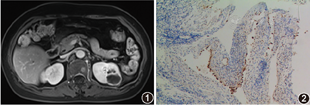

例1 女,64岁。2017年8月19日因无明显诱因出现左侧腰部间歇性疼痛,伴同侧腹痛8 d入院。查体无阳性体征。尿常规检查:白细胞计数35个/μl。CT检查:左肾上极见大小约3.7 cm×3.0 cm×3.0 cm类圆形低密度影,内见分隔,增强后分隔可见强化,皮质期、髓质期、排泄期CT值分别为111、118、120 HU。MRI检查:病变为3.1 cm×2.7 cm×3.4 cm大小的T1WI低、T2WI高信号灶,增强扫描大部分未见强化,其内可见分隔样强化(图1)。Bosniak分级为Ⅳ级。全麻下行腹腔镜根治性左肾切除术,术中见左肾中上极背侧一直径约4 cm×3 cm囊性肿块,囊内壁尚光滑。病理检查镜下见囊壁内衬单层立方上皮。免疫组化染色检查:上皮细胞CK、Vimentin和间质细胞SMA、ER、PR均阳性。病理诊断:肾脏混合性上皮-间质肿瘤(mixed epithelial and stromal tumor of the kidney,MESTK)。术后无特殊治疗,随访10个月未见肿瘤复发及转移。

例2 女,66岁。2018年5月2日因无明显诱因出现无痛性肉眼血尿10 d入院。查体阴性。尿液淡红色。尿常规检查:白细胞计数57.9个/μl,红细胞计数2 628.8个/μl,上皮细胞46.2个/μl。B超检查示右肾囊肿。CT检查:右肾中部见大小约5.4 cm×6.8 cm×3.4 cm类圆形密度稍高影伴低密度区,平扫CT值40 HU,增强扫描实性成分轻度强化,局部肾盏显示不清,邻近肾盂受压。Bosniak分级为Ⅳ级。全麻下行腹腔镜根治性右肾切除术,肿瘤呈多房性,囊内壁尚光滑,大小7.0 cm×5.5 cm×3.5 cm。病理检查镜下见部分囊壁内衬靴钉状细胞,囊壁间质细胞相对较丰富。免疫组化染色检查:上皮细胞CyclinD1(图2)和bcl-2阳性。病理诊断:MESTK。术后随访1.5年,未见影像学及临床复发、转移征象。